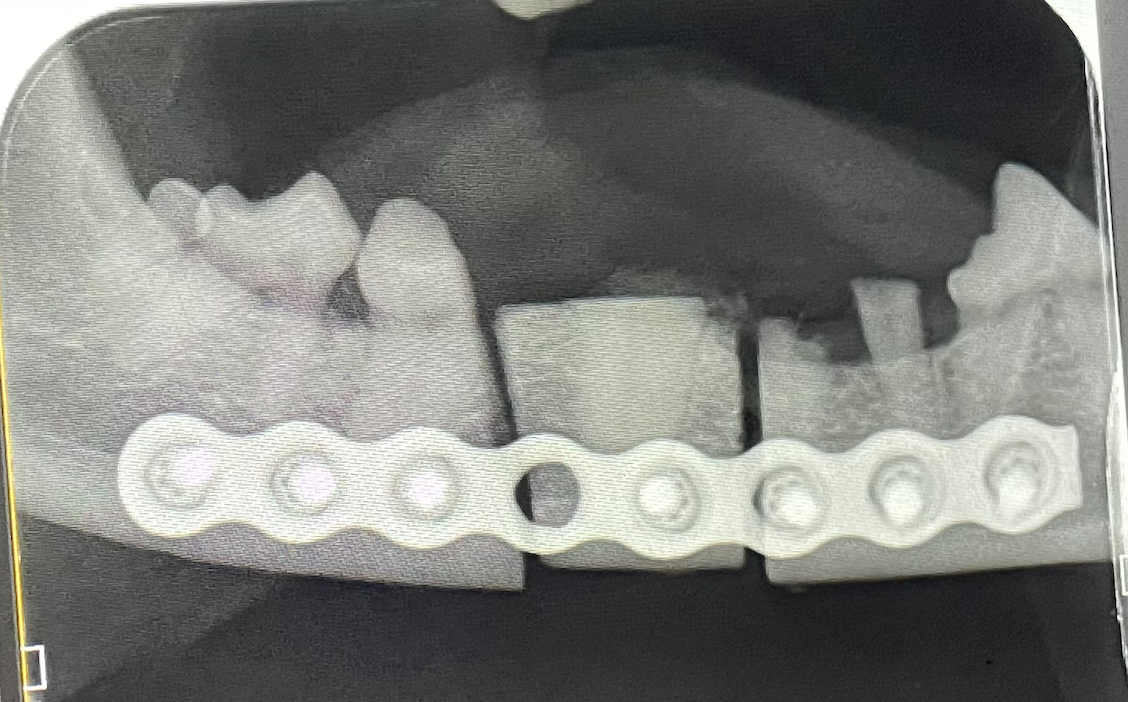

Eine internationale Gruppe von Tierzahnärzt:innen und Chirurg:innen kam Mitte Oktober in Tuttlingen für ein zweitägiges Intensivseminar bei Eickemeyer zusammen, um gemeinsam mit Prof. Alexander Reiter und seiner Assistentin, Dr. Kira Fraundorfer, die Möglichkeiten der Plattenosteosynthese in der Versorgung von Oromaxillofazialen Traumata zu erörtern und das neue System von Eickemeyer auszuprobieren. Ziel der Fortbildung war es, die Verwendung von Miniplatten zur Behandlung von Unterkiefer- und Oberkieferfrakturen sowie von Rekonstruktionsplatten und Knochenersatzprodukten zur Behandlung segmentaler Unterkieferdefekte zu erlernen.

Crina Dragu: Ja, ich hatte hier Assistenzerfahrung während der Residency an beiden Standorten. Vor allem bei ADVETIA gab es ein wahres fachliches Potpourri an Maxillofazialchirurgiefällen. Schon in meiner ersten Arbeitswoche durfte ich bei der Versorgung einer Hündin helfen, der ein schwerer Metallpfosten auf die Schnauze gefallen war, mit der Konsequenz einer imposanten Fraktur. Ich hatte aber noch keine Fälle komplett alleine versorgt. Daher wollte ich hierzu unbedingt mehr praktische Übung.